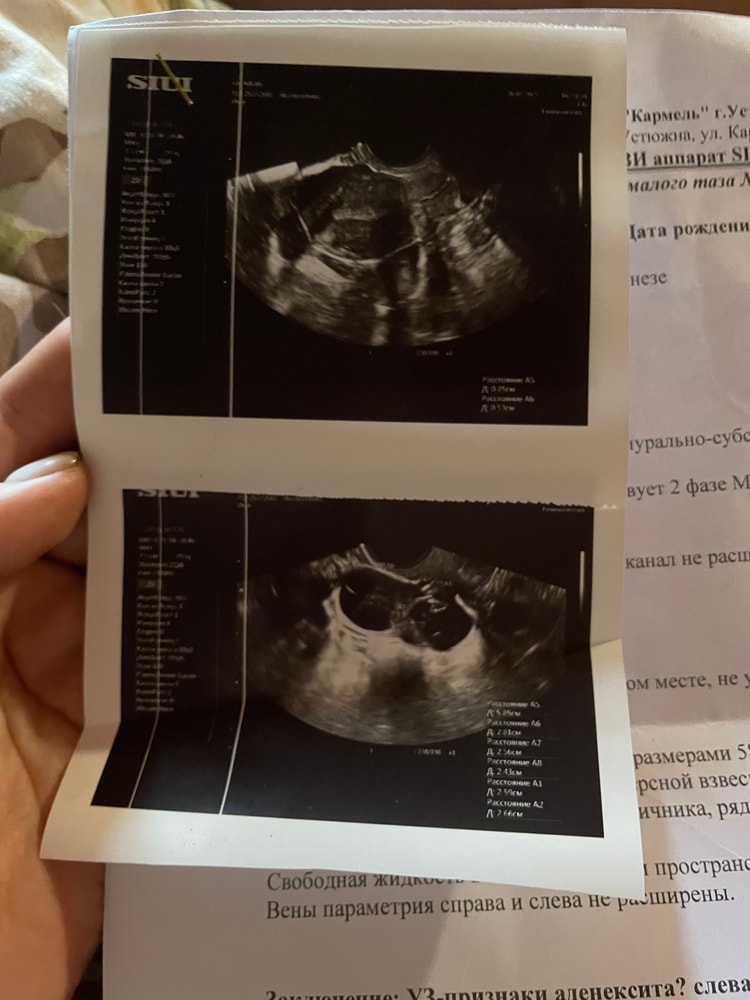

в прошлом месяце делала узи яичники были в норме. В этом месяце сделали узи и нашли кисту и расширение трубы

Подскажите не похожа ли эта киста на эндометриоидную ??? Очень переживаю